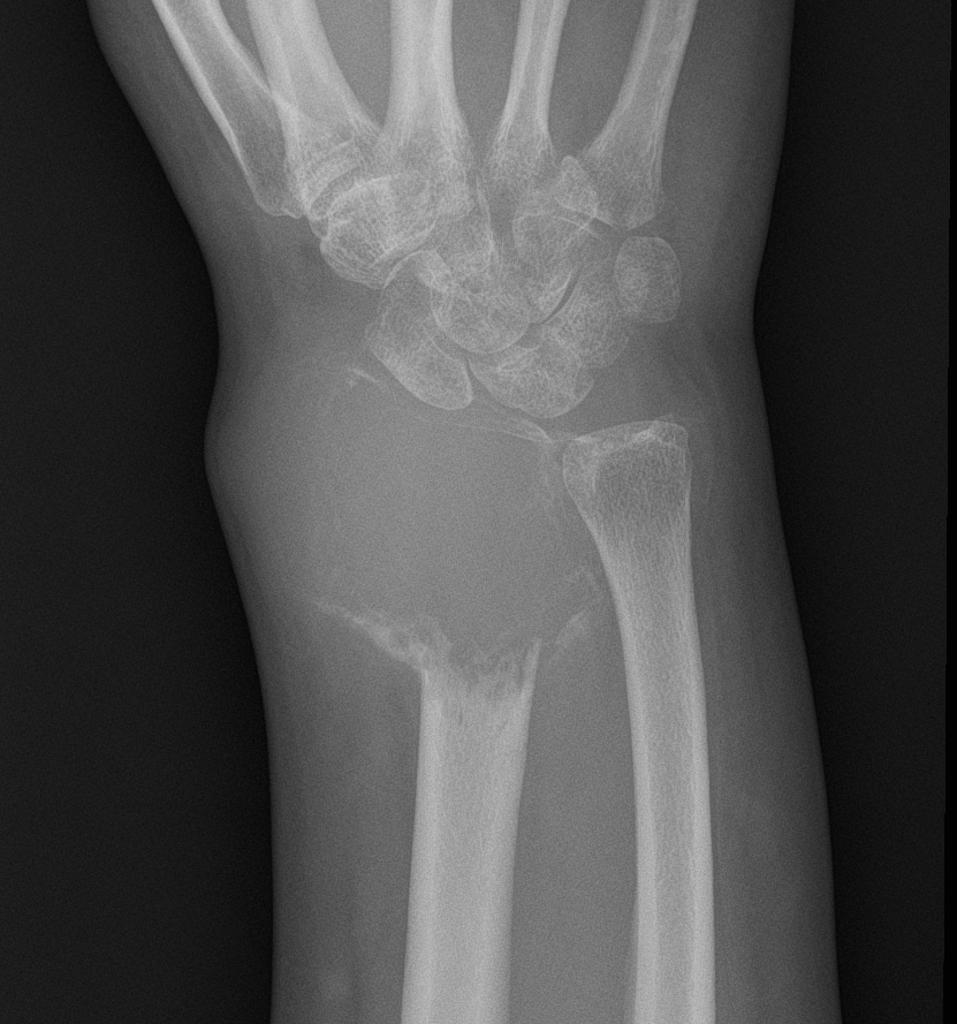

U tế bào khổng lồ là gì? Những điều cần biết về u tế bào khổng lồ